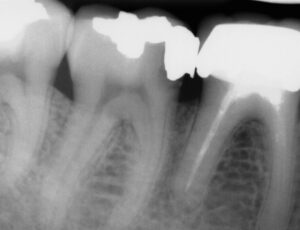

Biocompatible. Bioactive. Biological.

We use Bioactive restorative materials that release essential minerals (Calcium and Phosphate) back into your tooth.

This doesn’t just “fill” the hole—it helps the tooth structure regenerate and stay strong.